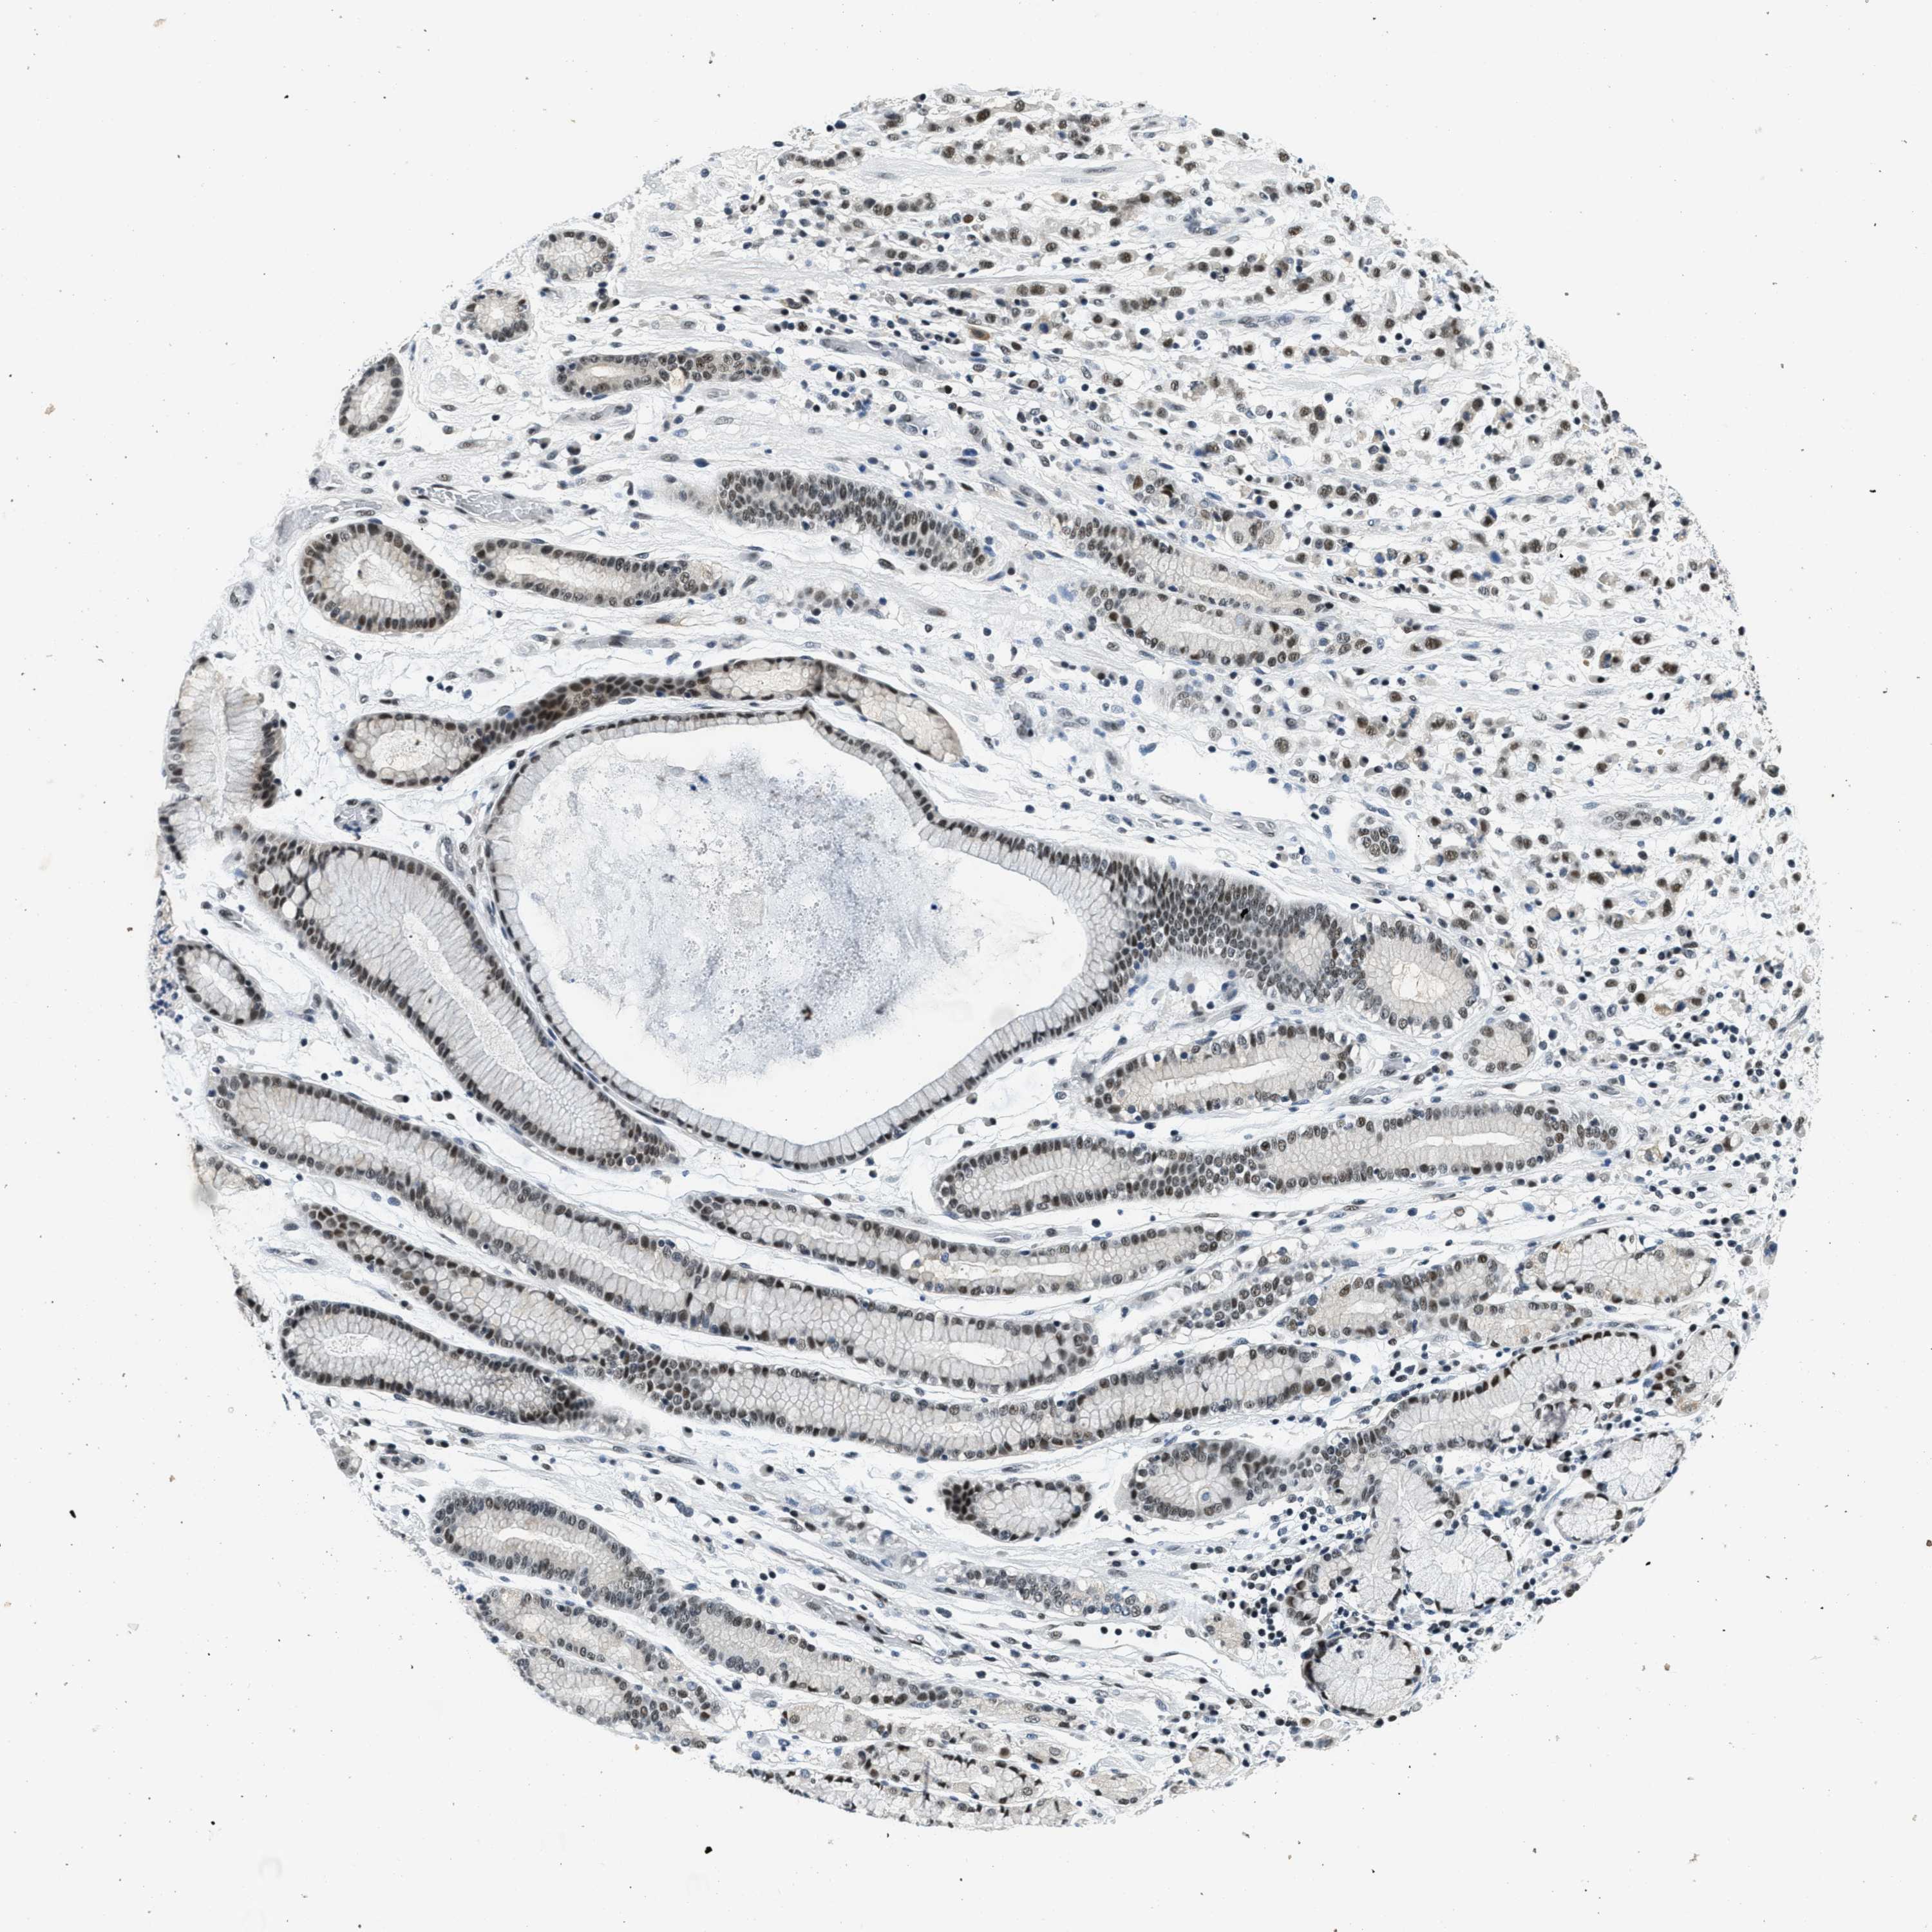

STOMACH CANCER - Protein expressioni

A mouse-over function shows sample information and annotation data. Click on an image to view it in a full screen mode. Samples can be filtered based on level of antibody staining by selecting one or several of the following categories: high, medium, low and not detected. The assay and annotation is described here.

Antibody stainingi

Antibody staining in the annotated cell types in the current human tissue is reported as not detected, low, medium, or high, based on conventional immunohistochemistry profiling in selected tissues. This score is based on the combination of the staining intensity and fraction of stained cells.

Each image is clickable and will lead to virtual microscopy that enables deeper exploration of all samples and also displays staining intensity scores, fraction scores and subcellular localization as well as patient and tissue information for each sample.

Antibody HPA017287

Antibody CAB004643

Staining

High

Medium

Low

Not detected

Intensity

Strong

Moderate

Weak

Negative

Quantity

>75%

75%-25%

<25%

None

Location

Nuclear

Cytoplasmic/membranous

Cytoplasmic/membranous,nuclear

Adenocarcinoma, NOS

Adenocarcinoma, High grade